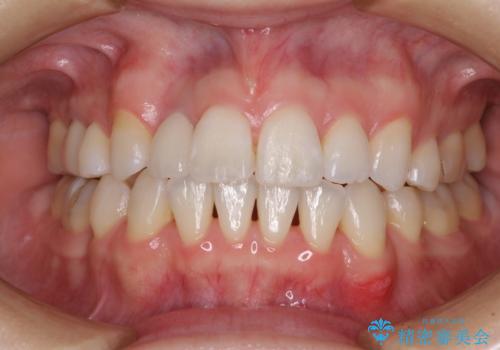

変色した前歯 オーダーメイドタイプのオールセラミッククラウン

- 虫歯により神経を取り除いた前歯の変色が気になるとのことで来院された患者様です。

他院で矯正治療をされていたそうですが、矯正治療前から変色は気になっており、歯並びが整ってからは、より気になるようになっていたそうです。

自然に仕上がり、患者様には大変満足していただきました。